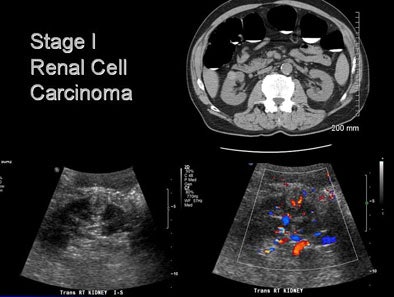

![]() |

| A man in his 70s underwent CT colonography screening; MDCT revealed a large renal mass. Workup also revealed multiple lung nodules. He was diagnosed with metastatic renal cell carcinoma; however, no intervention has been performed due to multiple comorbidities, and the patient has done well. |